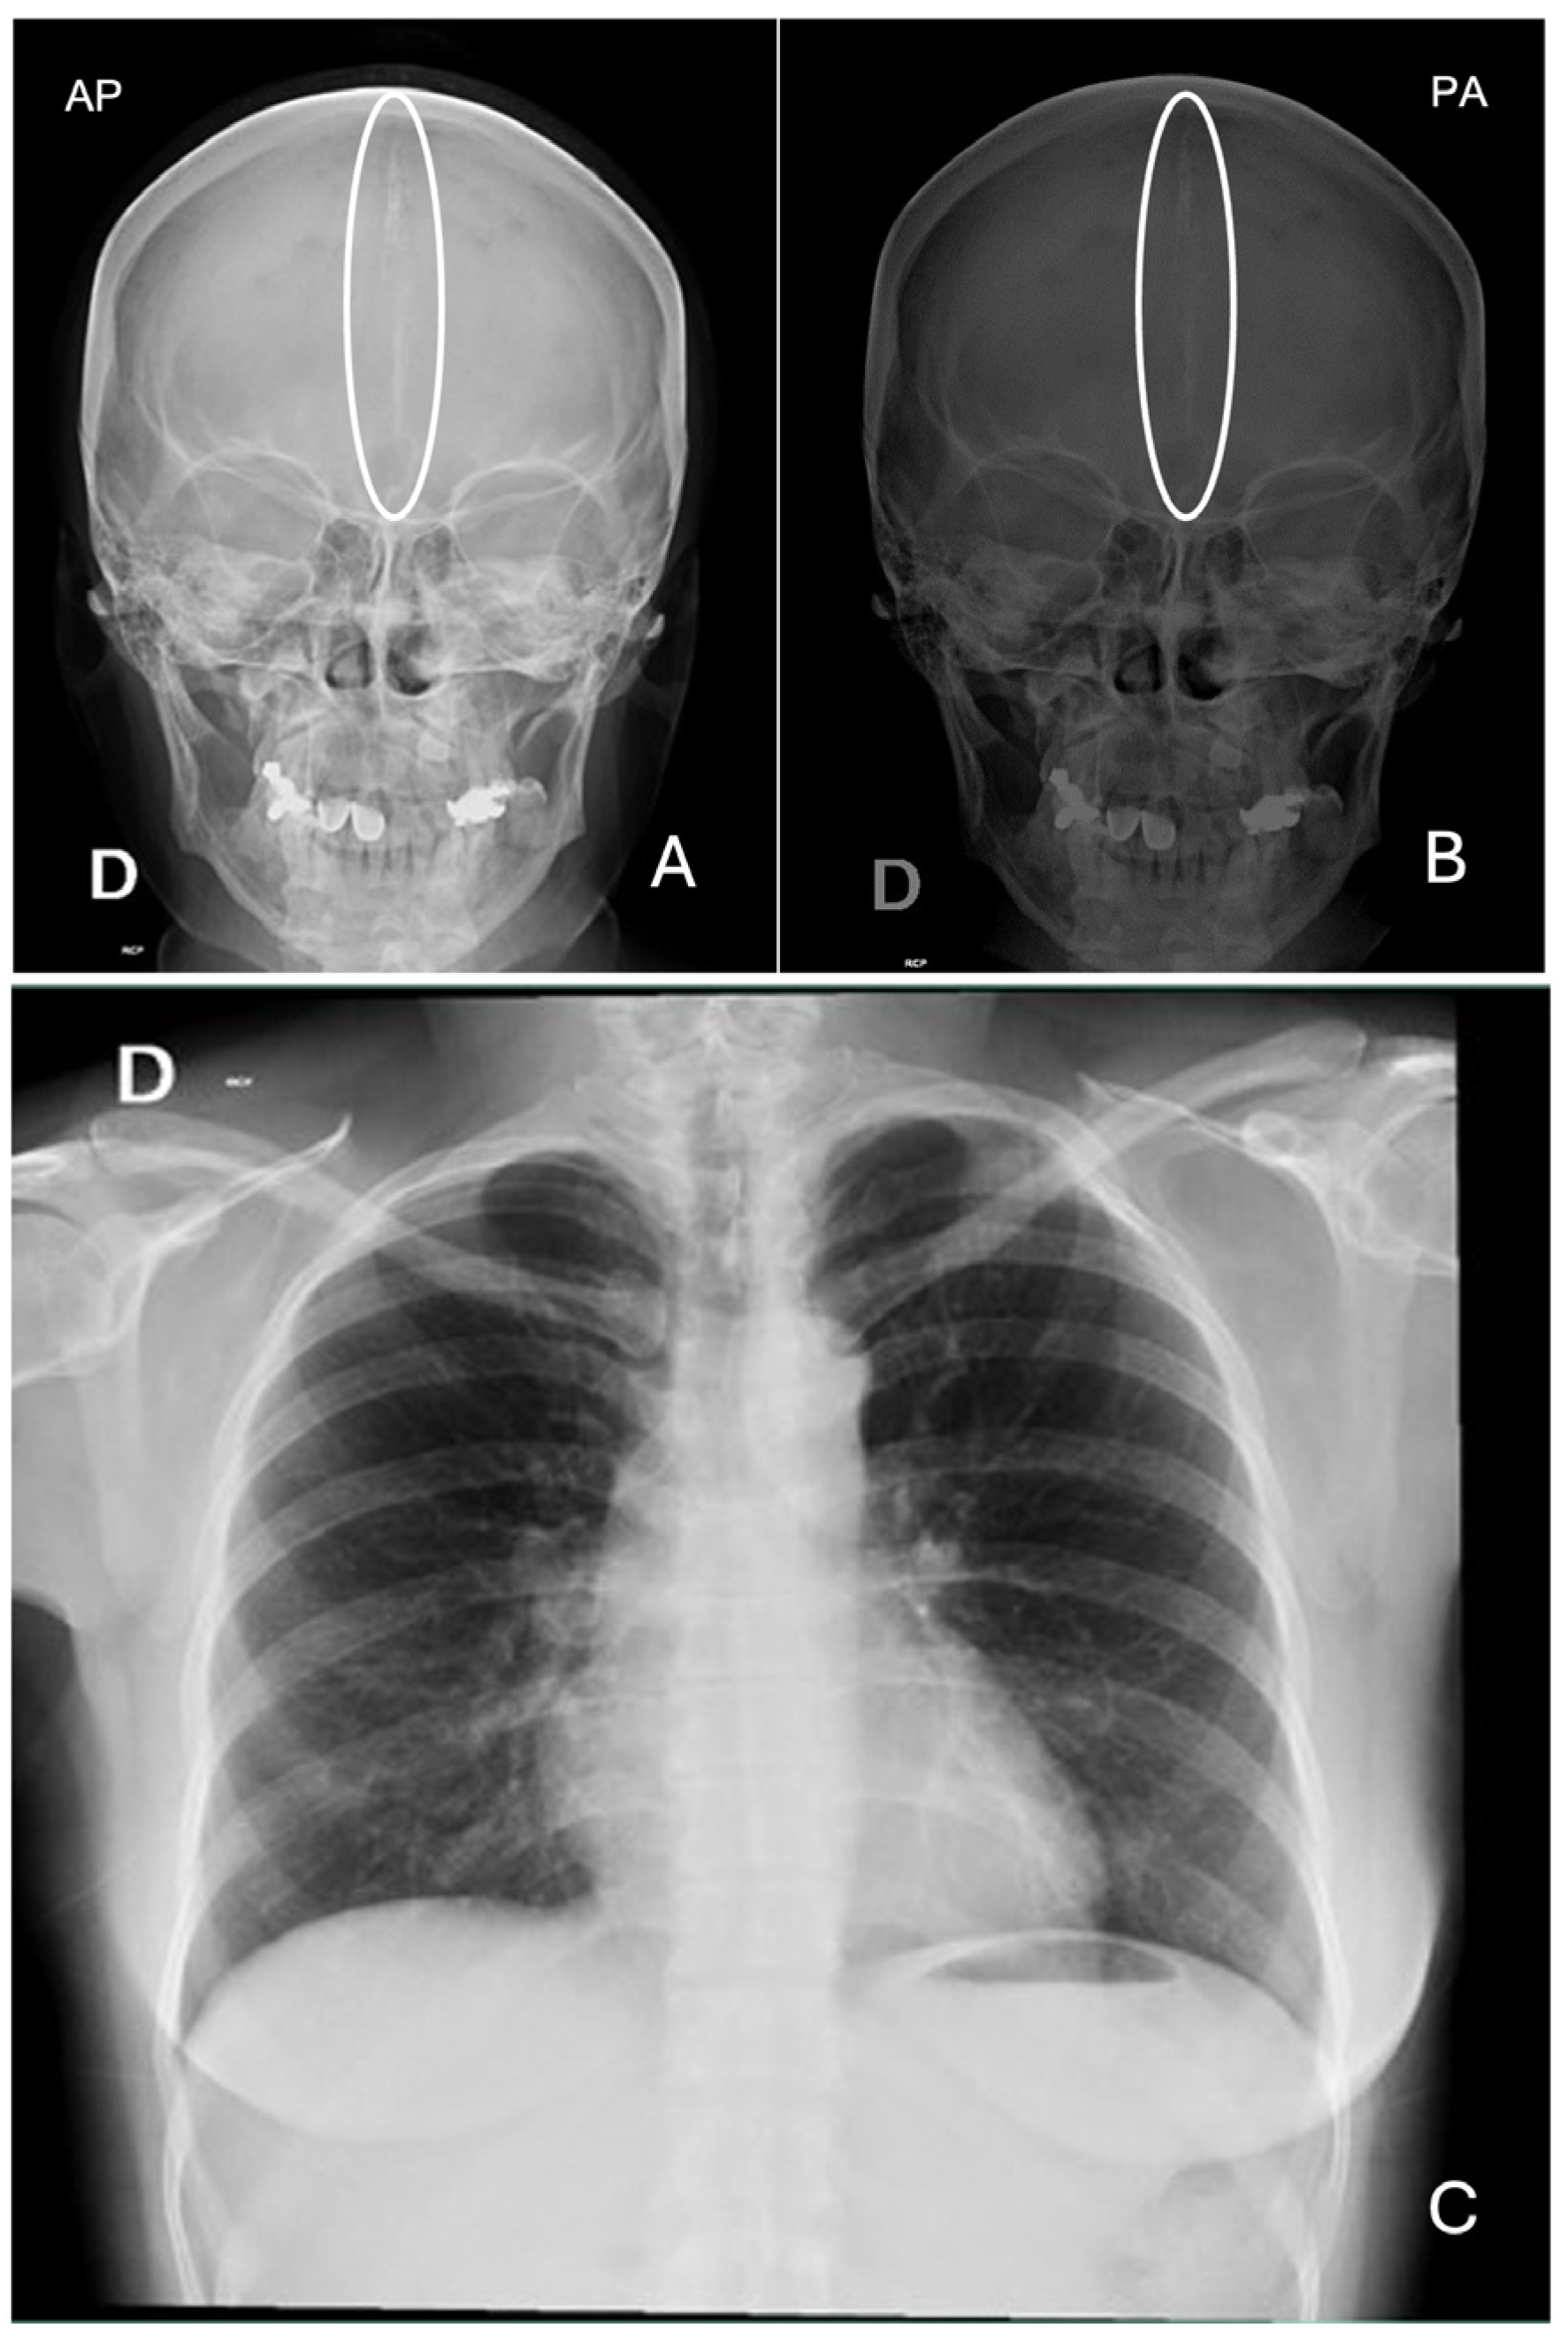

| Bilamellar calcification of the falx cerebri | Radiological abnormalities: pons sella turcica, vertebral abnormalities such as fusion or elongation of the vertebral bodies |